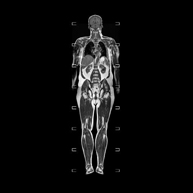

Prueba diagnóstica no invasiva que consiste en la obtención de imágenes de alta definición anatómica de la glándula prostática mediante el empleo de un campo electromagnético y ondas de radio (con un emisor y un receptor). No utiliza radiación ionizante. Se utiliza una bobina endorrectal para obtener imágenes de máxima definición anatómica de la próstata, que permitirá realizar el estudio espectroscópico (estudio a nivel molecular que ayuda a diferenciar las células de origen maligno o tumoral). También se realiza el estudio con contraste paramagnético que aporta una mejor definición tisular. Esta prueba dura unos 40 minutos, durante los cuales el paciente deberá estar lo más quieto posible. Como preparación previa requiere limpieza del colon. Esta prueba está especialmente indicada en aquellos pacientes con sospecha de neoplasia de próstata, con neoplasia de próstata conocida para el estadiaje tumoral, estudio de localización del tumor prostático como guía o mapa para la biopsia, seguimiento de los pacientes con neoplasia de próstata tratados con tratamiento quirúrgico o radioterápico, sospecha de recidiva de la neoplasia de próstata, etc. - RM Cuerpo entero (Total body)

Prueba diagnóstica no invasiva que consiste en la obtención de imágenes de alta definición anatómica de todo el cuerpo mediante el empleo de un campo electromagnético y ondas de radio (con un emisor y un receptor). No utiliza radiación ionizante. Es una prueba muy importante en la búsqueda de metástasis en pacientes con neoplasia conocida. No requiere preparación previa. No es necesario el empleo de contraste paramagnético (Gadolinio). - Angio-RM Aorta abdominal

- Complete spine MRI

This non-invasive diagnostic procedure uses an electromagnetic field and radio waves (from a transmitter and receiver) to acquire high-definition anatomical images of the cervical, thoracic and lumbar spine. It is a radiation-free procedure. Indicated for: detection of metastasis, scoliosis, trauma.